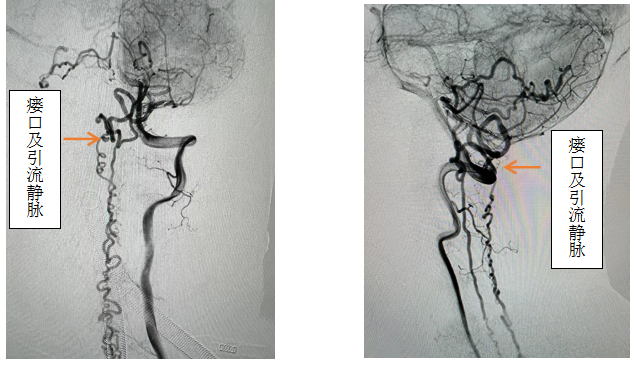

,效果欠佳。入院时已经行走困难,行颈椎核磁见颈椎蛛网膜下腔异常信号影,请神经外科会诊后考虑硬脊膜动静脉瘘可能性大,转入神外后立即由李帅主治医师行全脊髓血管造影,见“左侧椎动脉V4段发出脑膜支,其远端分支供血形成硬脊膜动静脉瘘,瘘口位于枕骨大孔区,经延髓背侧及腹侧向下引流至胸2椎体节段”。缪星宇主任主持全科病例讨论,讨论考虑患者经脊髓血管造影后诊断明确,手术指征明确,可行硬脊膜动静脉瘘介入栓塞术或开颅阻断术。术中可采取“高压锅”技术防止栓塞胶的返流,降低微导管的到位要求,降低返流空间的要求,使得返流空间安全可控,缩短注胶时间,增加胶的弥散效率,从一定程度上提高栓塞比例,增加患者的安全性。如介入微导管到位困难,可以考虑开颅阻断瘘口,但瘘口位置距离呼吸中枢延髓较近、术中风险大且术后患者恢复时间长。科室讨论后决定利用21点技巧中心

先进的复合手术室,首先采用第一方案“高压锅”技术使胶完全封堵瘘口,若不能到位或完全封堵,则采用第二方案,转为开颅阻断瘘口。手术当日,由黄卫东主任医师和李帅主治医师操作,第一根栓塞微导管顺利到达瘘口,第二根微导管接近栓塞微导管后使用弹簧圈顺利形成高压锅塞子,经第一根微导管注入栓塞胶,射线透视下见栓塞胶按预期流向瘘口,栓塞满意后造影示瘘口及引流静脉均未见显影,手术成功。术后患者恢复良好,第二天即下床活动,下肢活动明显恢复,5天后步行出院。